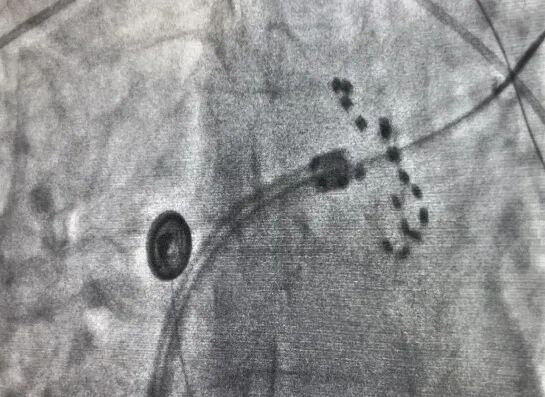

经过术前充分筹备,在手术团队、麻醉科、超声科和导管室医护人员的通力合作下,手术有条不紊的进行。术中将脉冲消融导管放置于肺静脉口部和前庭部位,通过脉冲消融系统释放2.0kv的脉冲电场能量至心肌组织,致使心肌细胞达到有效的、不可逆的损伤,消灭了病变的组织。

上图为X线下farapulse导管的两种形态:网篮状(左)和花瓣状(右)

脉冲消融术后,经验证患者的肺静脉均完成了电隔离。其中第一位患者脉冲消融时长为13分钟;第二位患者脉冲消融时长为25分钟,左心耳封堵时长20分钟,两台手术均高效完成,术后两名患者各项体征正常,安全返回病房,无任何并发症或不良事件。